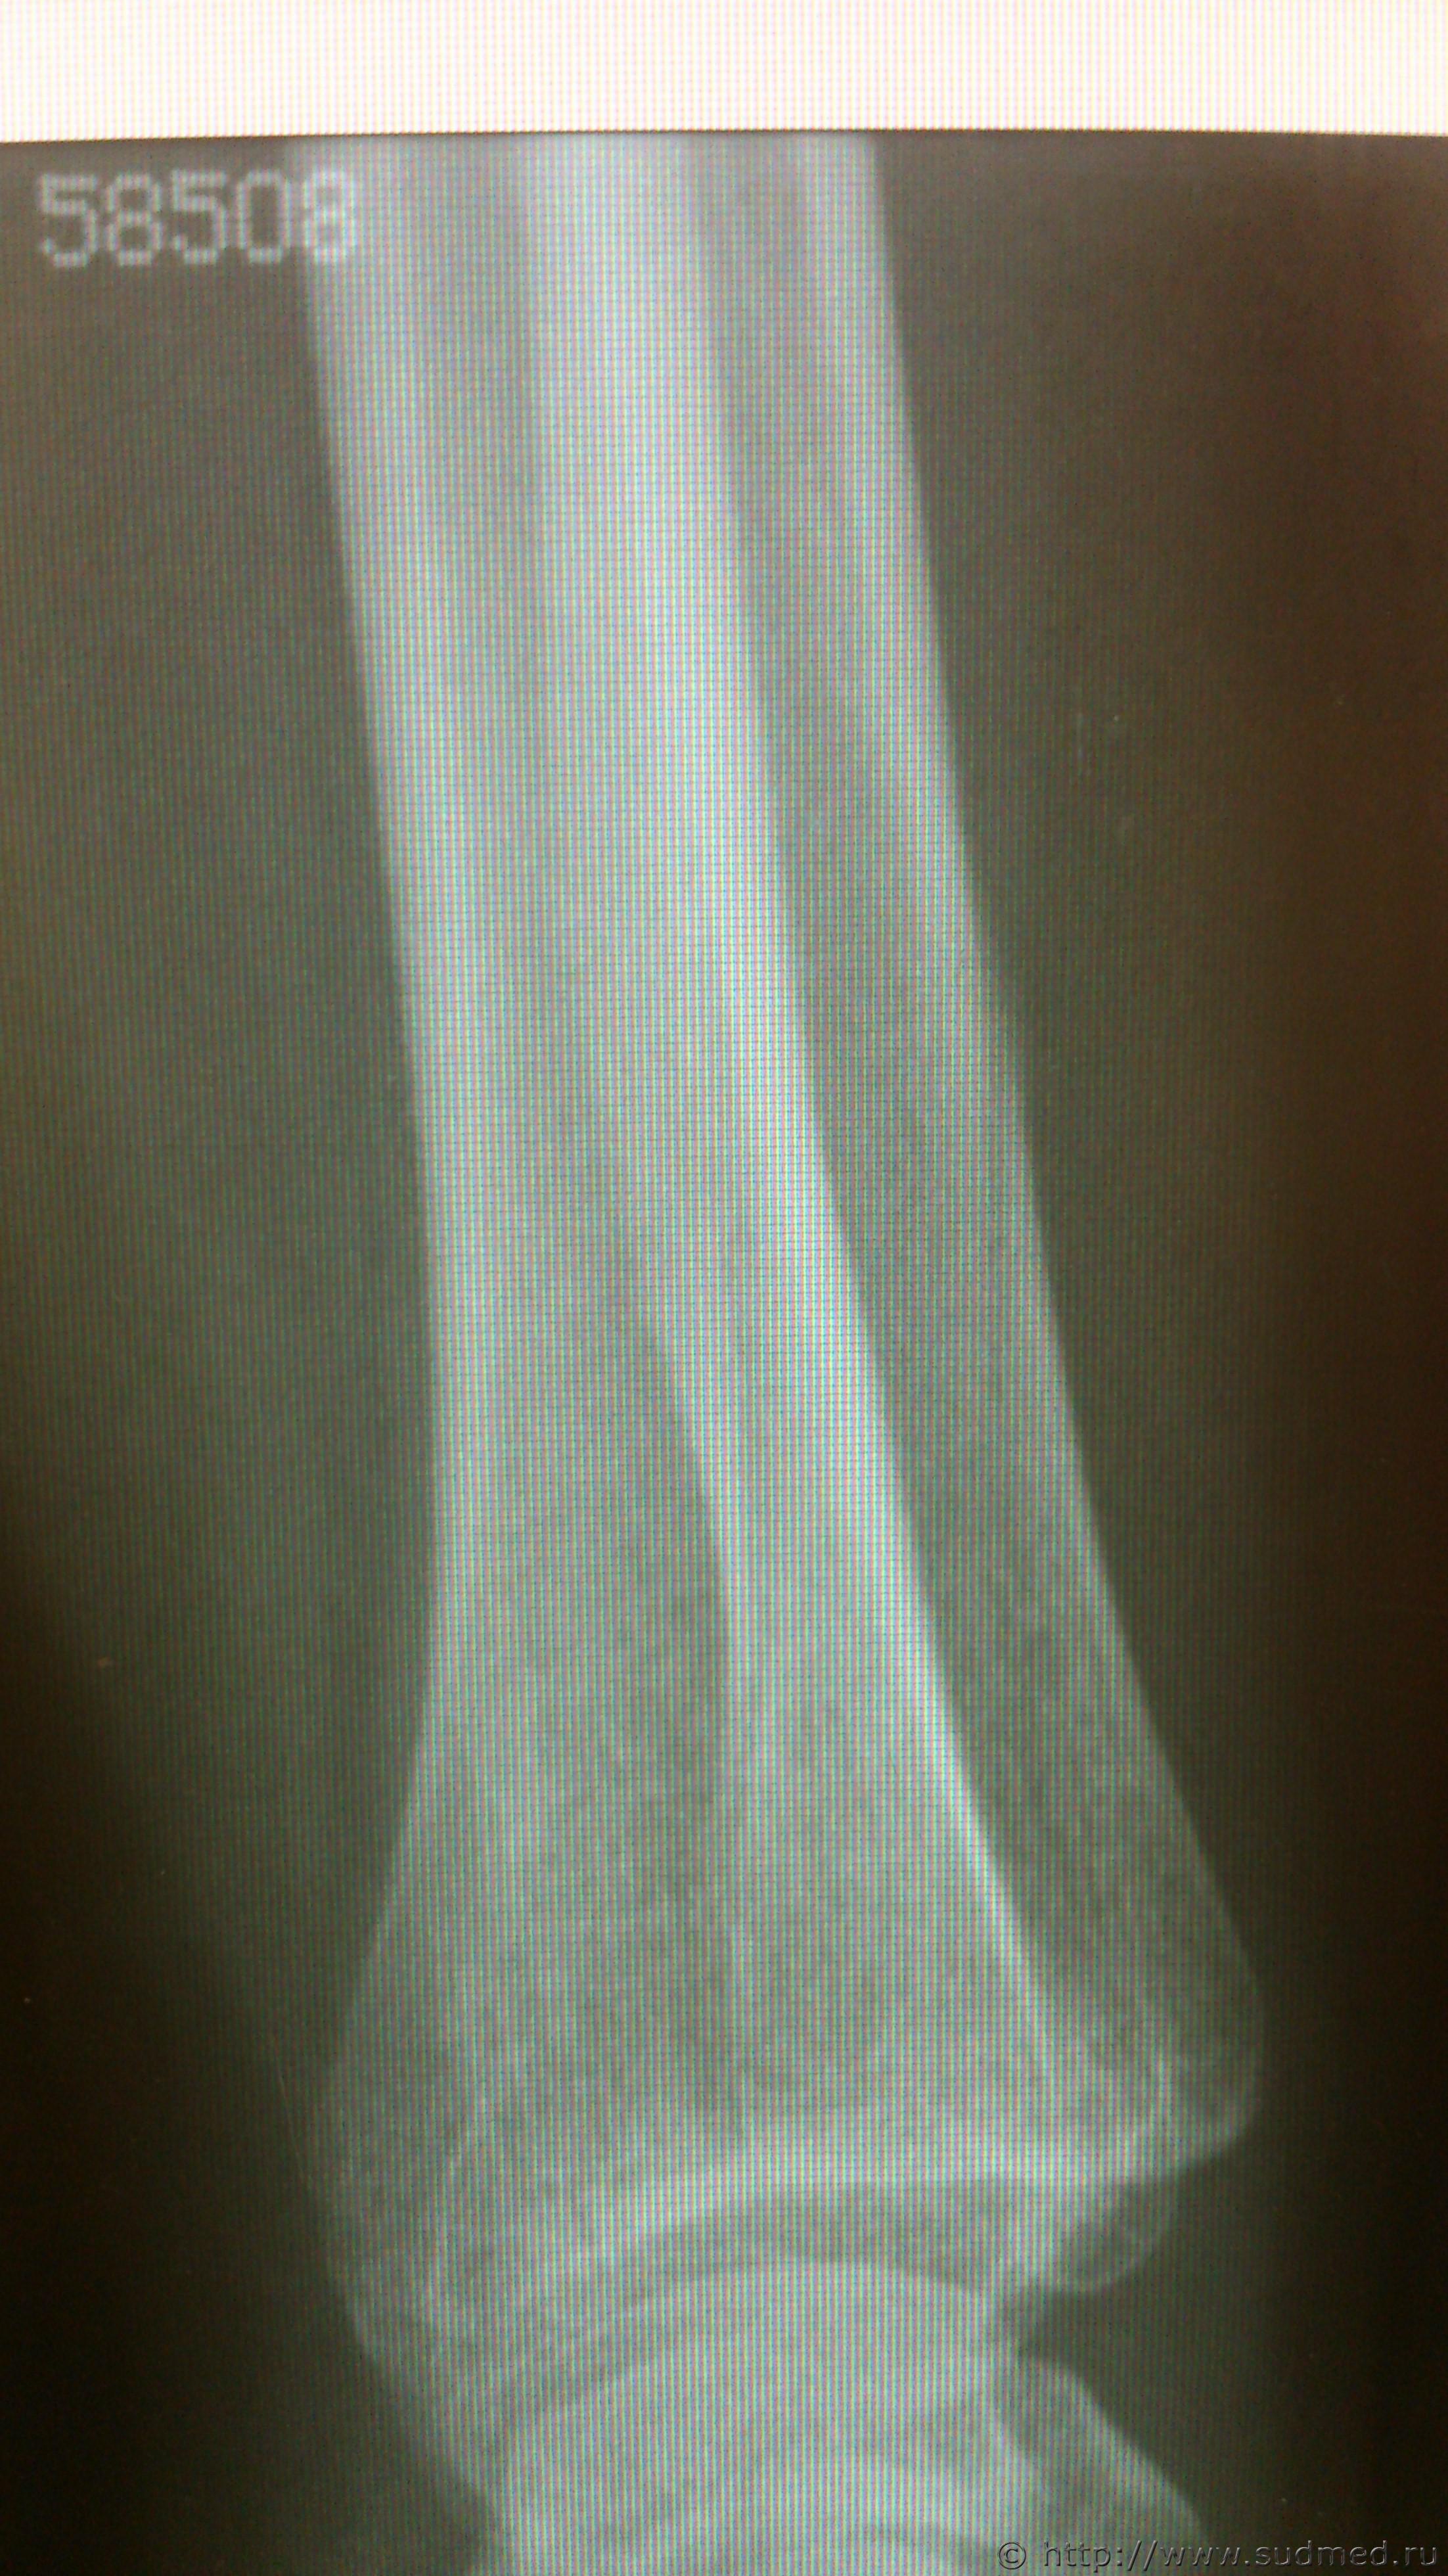

Здравствуйте, уважаемые коллеги! Возник вопрос по механизму образования перелома локтевой кости. Согласно описанию рентгенолога: «в нижней трети правой локтевой кости определяются два линейных просветления, направленных параллельно оси кости, шириной около 2,0 мм, с достаточно четкими контурами, без деформации оси кости, без видимой динамики рентгенологической картины между исследованиями (от 01.09.16 и от 07.10.16) – признаки консолидации не выявляются (отсутствует уплотнение костной структуры, костная мозоль не формируется)» Выводы: установлены признаки вертикального перелома правой локтевой кости в нижней трети без смещения отломков. Диагноз травмпункта: «Закрытый перелом ДМЭ правой локтевой кости со смещением отломков». По обстоятельствам - «нанес один удар деревянным стулом сверху-вниз, защищаясь от удара, лежа на кровати, подставила свою правую руку». Встречался ли кто-нибудь с такого рода переломами и есть ли соображения относительно механизма его образования.

Эскизы прикрепленных изображений

Судебная медицина - Прикрепленное изображение Судебная медицина - Прикрепленное изображение Судебная медицина - Прикрепленное изображение Судебная медицина - Прикрепленное изображение